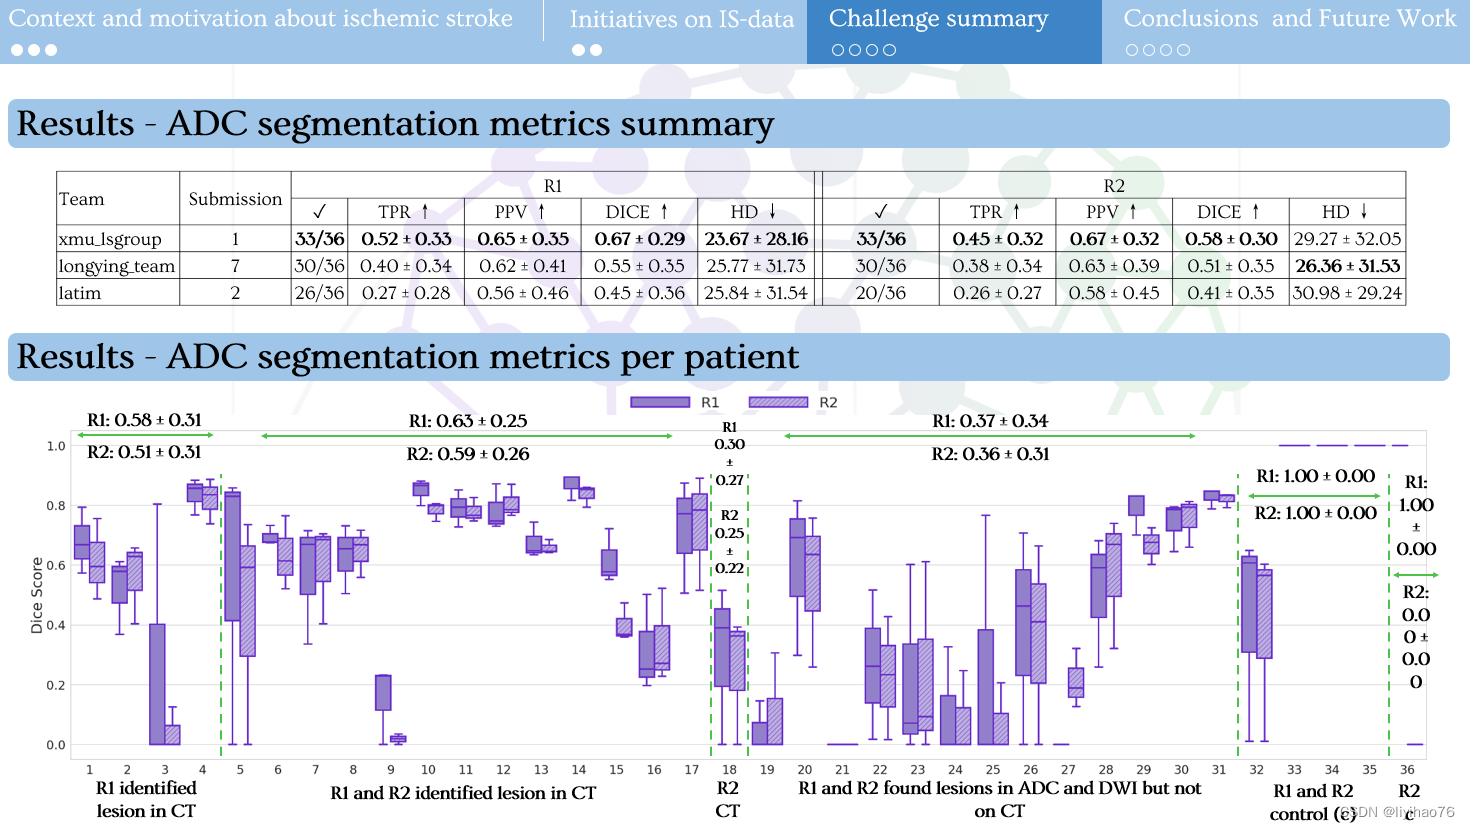

1.比赛任务及结果

5.比赛总结

- 由于病变的对比度差和低衰减,对缺血性中风 NCCT 序列的分割仍然具有挑战性。

- 目前在 ADC 序列上的工作可以以良好的性能分割病变,但在缺血病例的临床作用路径中是不可行的。

- 无论是模型、预处理还是其他方法都无法在 NCCT 序列上取得显着的结果。

- nnU-Net 在3D分割任务中依旧表现优异,数据预处理的不同可能会对分割表现有较大影响。